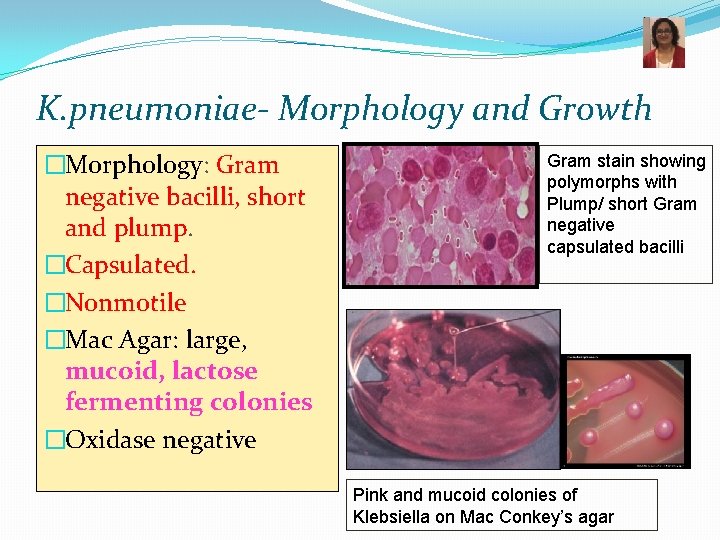

K. pneumoniae- Morphology and Growth �Morphology: Gram negative bacilli, short and plump. �Capsulated. �Nonmotile �Mac Agar: large, mucoid, lactose fermenting colonies �Oxidase negative Gram stain showing polymorphs with Plump/ short Gram negative capsulated bacilli Pink and mucoid colonies of Klebsiella on Mac Conkey’s agar